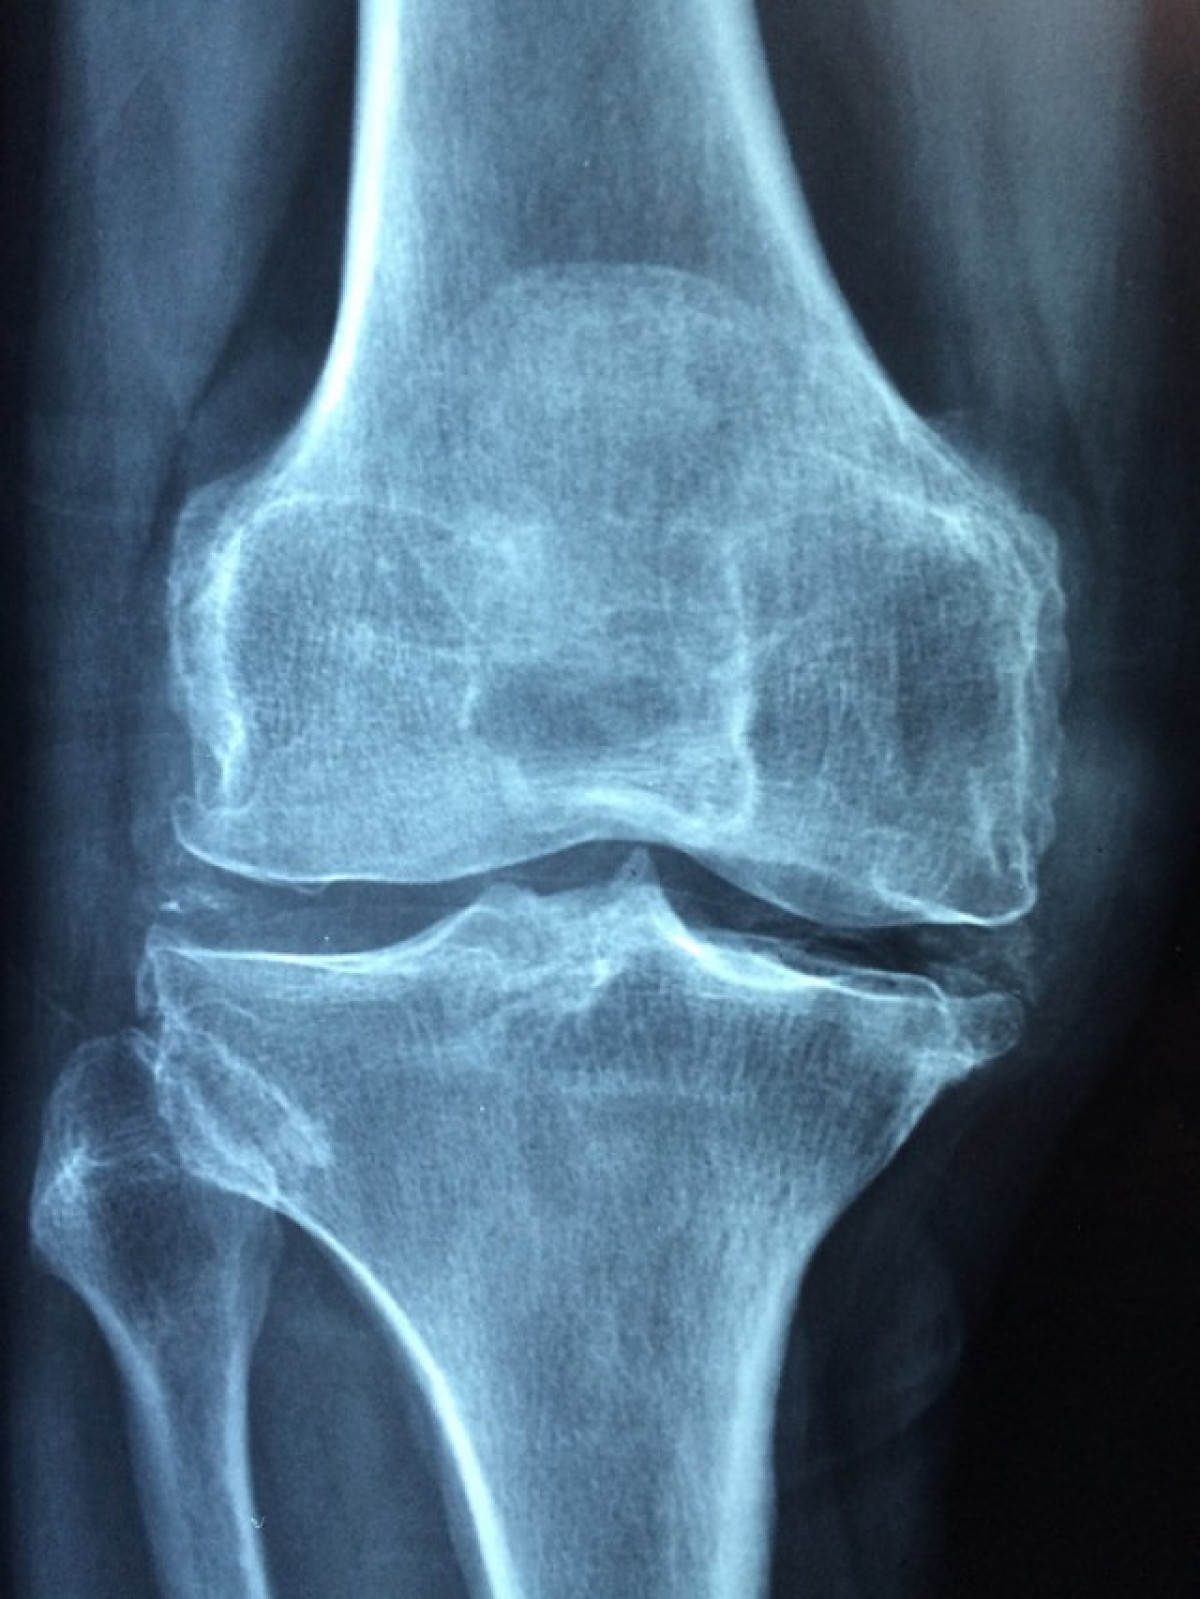

Van descobrir que l'edat del cartílag depenia en gran mesura d'on residia en el cos. El cartílag en els turmells és jove, de mitjana edat al genoll i vell als malucs. Aquesta correlació entre l'edat del cartílag humà i la seva ubicació en el cos s'alinea amb la forma en què es produeix la reparació de les extremitats en certs animals, que es regeneren més fàcilment en les puntes més llunyanes, inclosos els extrems de les potes o les cues.

La troballa també ajuda a explicar per què les lesions als genolls de les persones i, especialment, els malucs triguen molt a recuperar-se i, sovint, es converteixen en artritis, mentre que les lesions als turmells es curen més ràpid i amb menys freqüència es tornen severament artrítiques.